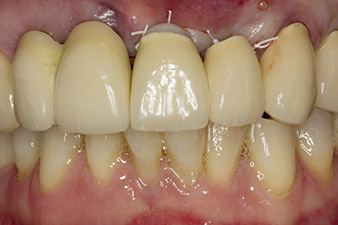

Following primary healing, the soft tissues were shaped using the basally lined bridge. Two months later the site was exposed by a slightly palatal alveolar ridge incision (Fig 2). The dimensions of the alveolar bone proved to be sufficient at position 22. Figures 2 and 4 show the preparation of the implant bed, the tapping and the implantation using Implantmed.

pilot drilling is performed with the new Implantmed and the WS-56 L contra-angle handpiece

Fig. 2: Two months later the pilot drilling is performed with the new Implantmed and the WS-56 L contra-angle handpiece (programme P1, ratio 1:1). The cooling is performed via the spray tube positioned on the left (for right-handed users).